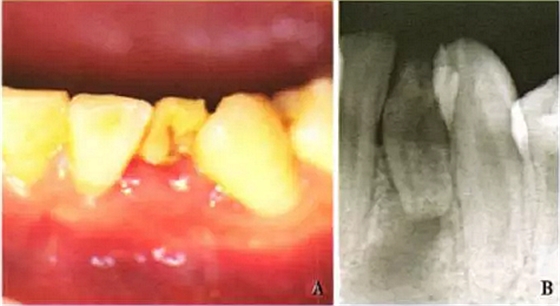

患者,男,17歲,因下頜左前牙區(qū)自發(fā)痛咬合痛4d前來就診??谕鈾z查未見明顯異常,口內(nèi)檢查見32(FDI牙位表示法)牙冠形態(tài)異常,舌側(cè)窩較對側(cè)同名牙深,唇側(cè)有一深凹陷(圖1A);32叩診陽性,牙髓活力測顯示無牙髓活力,I度松動;唇側(cè)牙齦略紅腫,探診出血,未探及牙周袋;鄰牙未見明顯異常。根尖片示32牙冠與牙根形態(tài)異常,且牙根短小,其根尖周圍見x線透射區(qū)(圖1B)。

A:口內(nèi)唇側(cè)像示下頜左側(cè)切牙牙冠異常;B:32牙內(nèi)陷,根尖周圍較大范圍X透射區(qū)

圖1 32牙內(nèi)陷